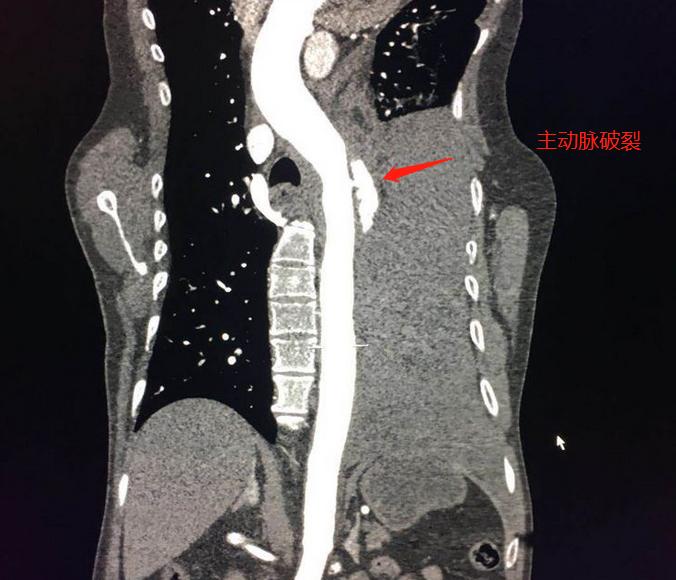

左侧大量胸腔积液,并且有分层现象,提示有为胸腔出血,考虑主动脉破裂,建议紧急CTA(主动脉造影检查)明确病变部位和范围。

胸外科主任在旁边监测生命体征,放射科主任亲自扫描,30分钟内完成造影扫描、后处理、出具影像报告(第2道):

主动脉弓部见不规则瘤样扩张影,以窄径与主动脉相连,符合壁间血肿并假性动脉瘤、穿透性溃疡。需要马上手术修补封堵。